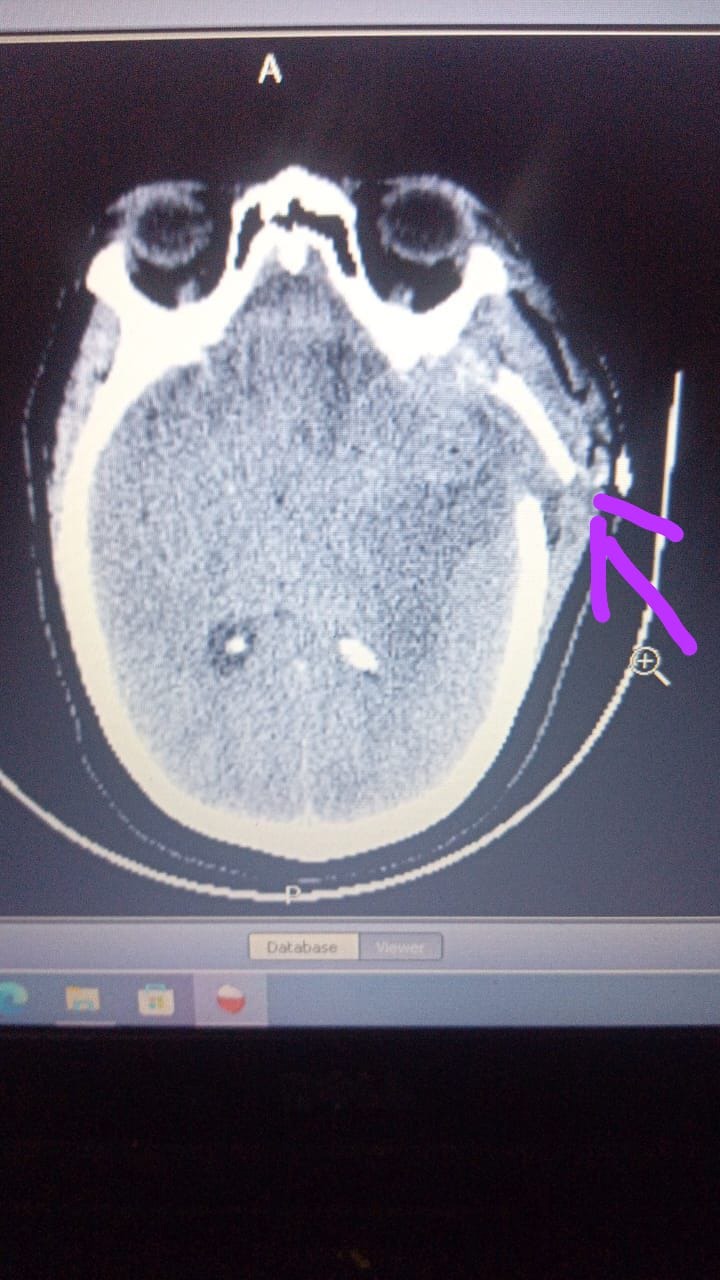

Hola, Bendiciones. Mi nombre es Lidia Urbaez, Discúlpeme por hacer esta petición. Mi solicitud de su ayuda, es por una urgencia médica  que tengo de emergencia. Mi situación es que hace unos días me realize una intervención quirúrgica la cual no se realizó efectivamente, y ya hice los gastos que correspondía a la misma. El médico que me realizó dicha intervención no la realizó bien, por esto me decidí consultar con otro doctor, el cual me confirmo que no me realizó bien la intervención. Por eso decidí realizarme nuevamente la extracción de la parte del tumor que no me sacaron, pero el costo de mismo es similar a lo que ya pagué. Lo cual es imposible para mi en este momento, por eso busco ayuda ya que no soy de una familia con recursos y las amistades, amigos y familiares qué tengo cercanos fueron los que pagaron la primera intervención. Por eso estoy buscando otras ayudas, esperando que me puedan colaborar para poder realizar la cirugía que necesito lo antes posible.